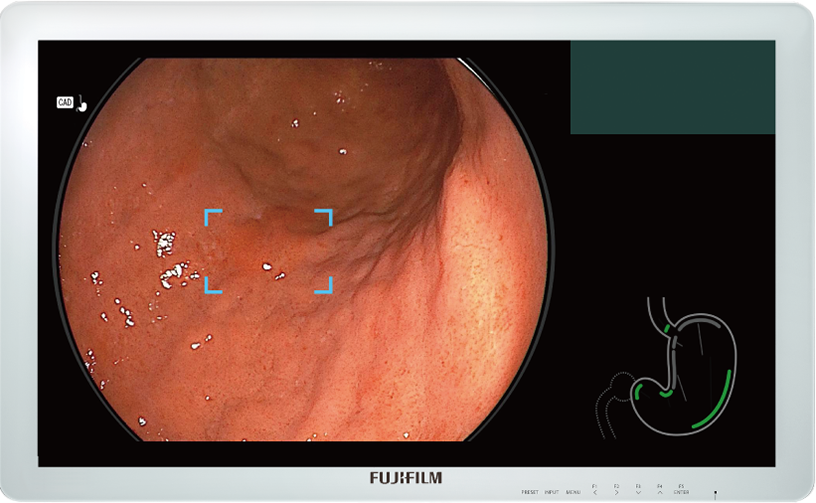

Detects the area that may be gastric neoplastic lesion and displays it on the main monitor in real-time.

Detection Box

Indicates the area where this software suspects that a lesion is present.

When a still image is captured, Landmark Photo Checker is activated to check if the major landmarks in the stomach are properly captured.

Before examination (Left) Complete state (Right)

Graphical user interface of CAD EYE is integrated and displayed together with an endoscopic image on a single monitor. It does not interfere with clinical images and minimizes required eye movement.